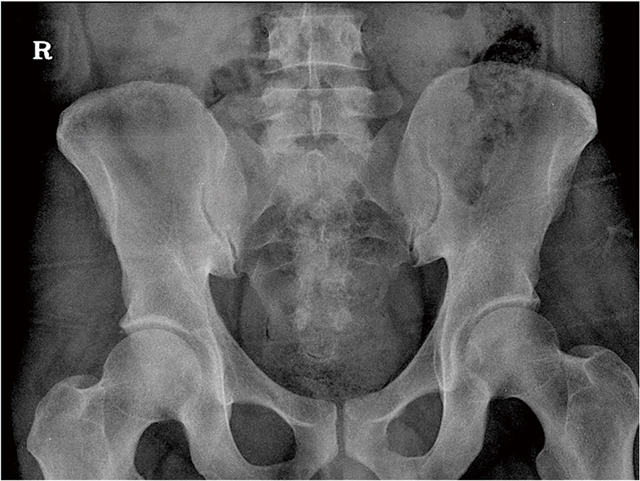

정상인의 골반 엑스레이.

강직척추염 환자의 골반 엑스레이.